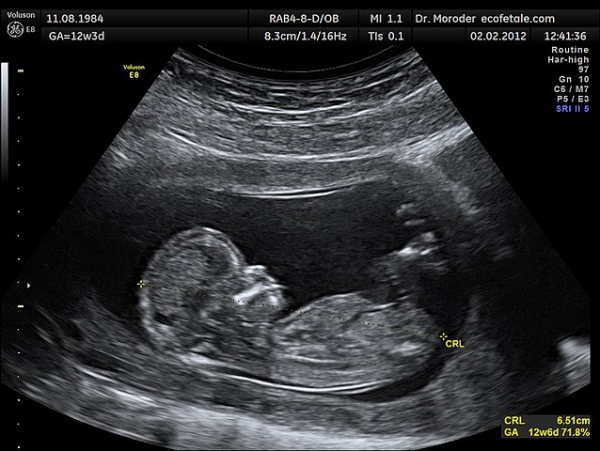

الشركة المغربية الناشئة "ديبيتشو" تطرح حلا طبيا للولادة المبكرة

طورت الشركة الناشئة المغربية "ديبيتشو" حلا يمكن أن يلعب دورا مهما في الكشف عن العيوب ومعالجة مشاكل الولادة المبكرة وتأخر نمو الجنين والنتائج الخطيرة المحتملة المرتبطة بها. وأبرزت الشركة، في بلاغ لها، أن هذا الحل يعد بالغ الأهمية، خاصة في المناطق التي تعاني فيها المستشفيات عموما من نقص في الموظفين والموارد.